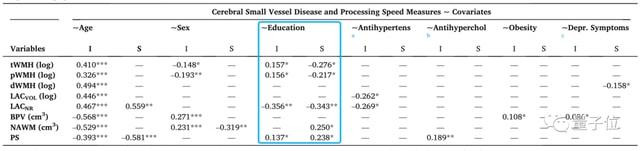

单看年龄、性别、教育等方面因素,下表中I表示为线性关系函数的截距,S表示为线性关系函数的斜率。

其中,年龄与WMH呈正比例关系,随着年龄增大、WMH增多。

教育背景则与WMH呈反比例关系,即所受教育程度越高,WMH增多越不明显。

而且研究人员发现,不只是大脑中的变化,学历背景越高的老人社交活动更为丰富,心理健康水平下降也更不明显。